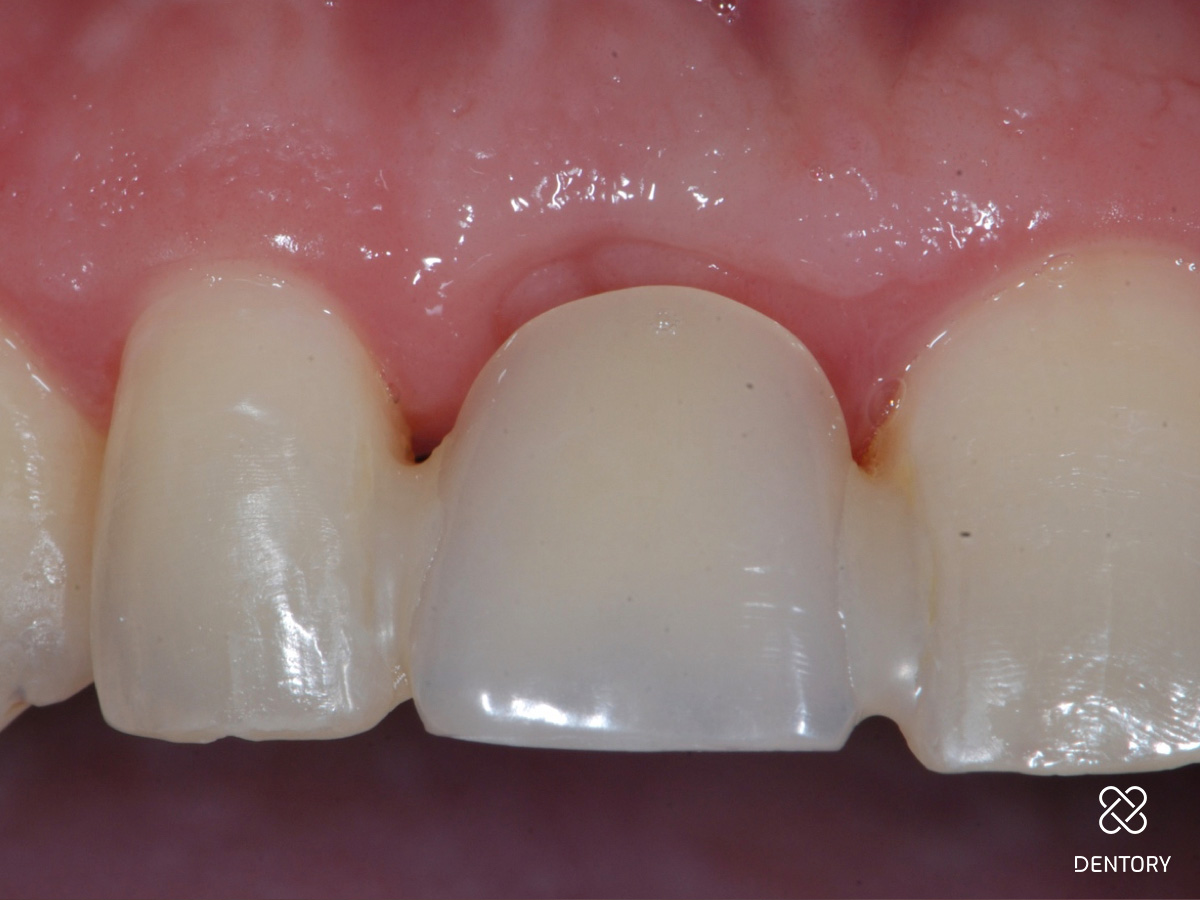

Abbildung 1

Ausgangssituation: Frontalansicht.